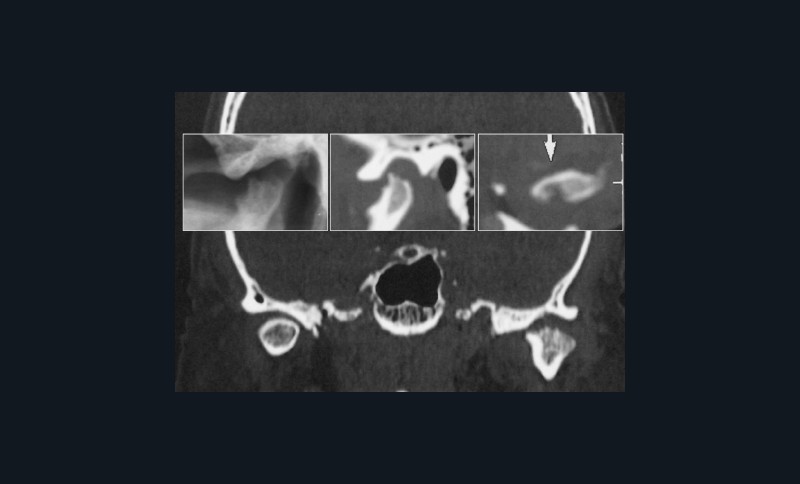

ATM : atteinte dégénérative de l’ATM gauche éventuellement en évolution.

Arthrite dégénérative de l’ATM gauche s’inscrivant

probablement dans un trouble systémique.